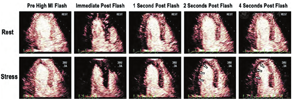

当使用血管扩张剂负荷时,使用高机械指数闪击破坏再充填技术是必不可少的,并且该技术可能比在需求负荷时更重要,由于氧耗显著增加,即使不用这种闪击-再充填技术,灌注缺损也可变得很明显。使用血管扩张剂负荷的RTMCE可用定量技术进行评估,并允许测定心肌血流量及其负荷/静息比值(血流储备),尽管对于该技术的可行性存在一些争议,总体认为其与其他可选择的技术相当[43,44,51]。

视觉定性分析更容易学习和减少劳动强度(图7和图8,视频10;可从www.onlinejase.com获得)。以下经验法则可用于结果判读:使用2D超声探头进行静息再充填应该在高机械指数脉冲闪击破坏后5 s内,在负荷状态下应2 s内再充填(视频6和7;在www.onlinejase.com获取)[1]。

在进行心肌增强超声心动图灌注成像时,如评估再灌注治疗对心肌梗死的疗效或评估心肌存活情况,会出现"有或无"两种灌注情况。对于这些情况,我们只需要评估微血管是否完整[91,92]。在MCE中,通过团注和连续输注UEA已经可以进行心肌血流量和容量的定量评估。测量快速团注UEA后首过的技术,联合其他无创成像技术,已经应用于MCE[93]。然而,这种方法并不推荐用于MCE,因为难以做到:①在造影剂首次通过心脏时对整个心脏进行成像;②充分考虑到在造影剂从静脉转运至全身时的扩散与分布。为此,我们对MCE的灌注成像技术进行了改进,测量灌注成像的两个主要参数:①灌注活跃的微血管单位的实时数量(微血管血流量[MBV]),②通过这些微血管的血流速率[94],这些参数的测量依赖于超声能量可影响微泡完整性这种独特能力[94,95]。大于0.8的高机械指数可破坏微循环内的微泡,从而消除它们的增强信号。微泡再入微循环的局部时间强度分析可评估微泡再填充的速率和程度,这分别反映了微循环通过速率和心肌血流量(MBV)(图9)。这个方法推荐使用于:①通过连续注射来维持循环中稳定的微泡浓度;②仅使用几个高能量的"闪击"信号(避免影响循环的浓度);③仅分析心脏收缩末期图像帧(消除来自心肌内大血管的信号)[96,97]。写作组发现,小剂量单次注射UEA并进行缓慢盐水冲洗,在注射后的一段时间内微泡浓度符合稳态动力学,且在临床中已用于检测信号再填充和MBV[53,55]。去除本底影响的信号强度数据可以拟合成指数方程:Y=A[1-e(-βt)],其中y是闪击脉冲后任何时间t时的造影剂信号强度,A是造影剂到达平台期的信号强度,反映相对MBV,速率常数β(s-1)反映微泡通过微循环的速率[94]。血容量和血流速度的乘积(A·β)是心肌血流量的半定量指数,而绝对血流量可以通过将A值以血池信号标化得到绝对的MBV。

在任何形式的负荷成像过程中,二维成像平面的再充填应该是一致的,并且静息状态在5 s内、负荷状态下在2 s内再充填。图11显示了高机械指数脉冲后正常的静息状态和负荷后的再充盈情况。图12和图13是在多巴酚丁胺负荷期间不同冠状动脉区域中诱导的心肌灌注缺损的示例。